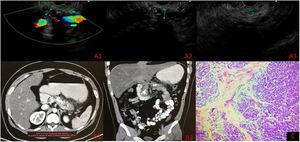

Case 2A 22-year-old man had a past medical history of numerous hospital admissions due to severe acute pancreatitis of biliary origin, from 2017 to the present date (eight hospital admissions). EUS identified signs of CP, MPD dilation, and intraparenchymal calcifications in the head, body, and tail of the pancreas and inside the MPD (Fig. 1A1–A3). Contrast-enhanced abdominal computed tomography scan revealed CP with multiple calcifications (Fig. 1B1–B2). The laparoendoscopic modified Puestow procedure with pancreatic biopsy was performed on September 2, 2021, confirming CP, with extensive fibrosis, associated with chronic inflammation (Fig. 1C). Oral diet was started the same day, in the afternoon, and the patient was released from the hospital 48 h after the procedure, with no complications.

A) Endoscopic ultrasound with main pancreatic duct measurement. A1) Neck 7 mm. A2) Body 10 mm. A3) Tail 3 mm (intraductal calcifications in body and tail). B1-B2) Contrast-enhanced abdominal computed tomography scan. C) Histopathology: chronic pancreatitis with extensive fibrosis associated with chronic inflammation.